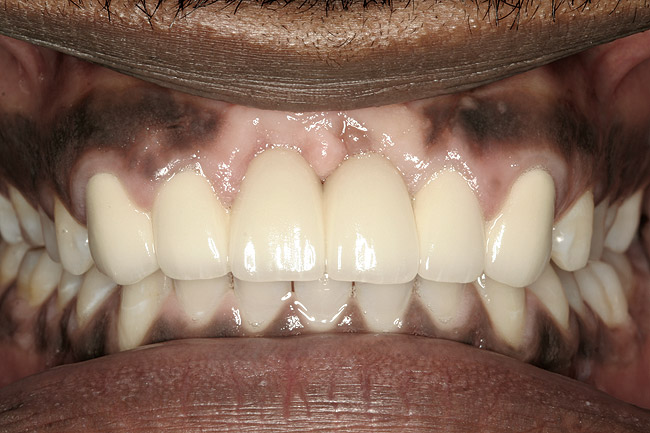

Figure 15 ENDODONTIC AND ESTHETIC PARAMETERS  The same teeth after crown lengthening and a new restoration created a more esthetically pleasing 80% height-to-width ratio.

Figure 15

Figure 16  ENDODONTIC AND ESTHETIC PARAMETERS  Gingival symmetry is defined as an imaginary line that should be collinear connecting the central incisors and canines. The gingival margin of the lateral incisor should be even with or coronal to this line by a maximum of 3 mm.

Figure 16